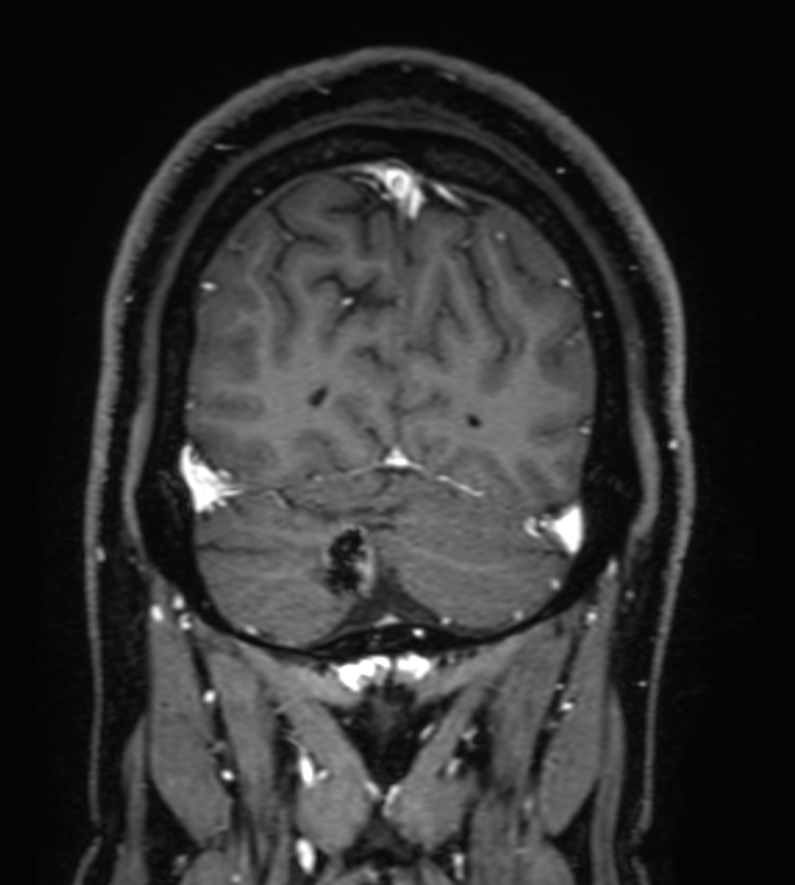

T1w FFE post-gado Compressed SENSE

3D T1w FFE FatSat post-gado Compressed SENSE